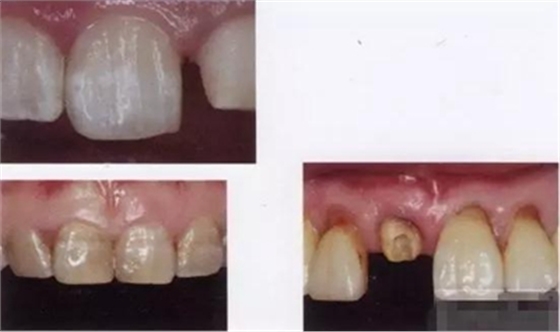

【主訴】上前牙充填物脫落兩個(gè)月

【病史】上前牙一年前行根管治療,充填物部分脫落,自覺影響美觀,從不敢笑,要求先行樹脂修復(fù)。(年齡:14歲)

【檢查】12,11,21,22,均行玻璃離子充填,各牙不同程度部分充填物脫落,探(—),叩(—),冷刺激無反應(yīng),無松動(dòng),牙齦顏色粉紅,質(zhì)地堅(jiān)實(shí)而有彈性,點(diǎn)彩正常,牙結(jié)石(—);牙髓活力測試無反應(yīng)。

【診斷】12,11,21,22牙體缺損